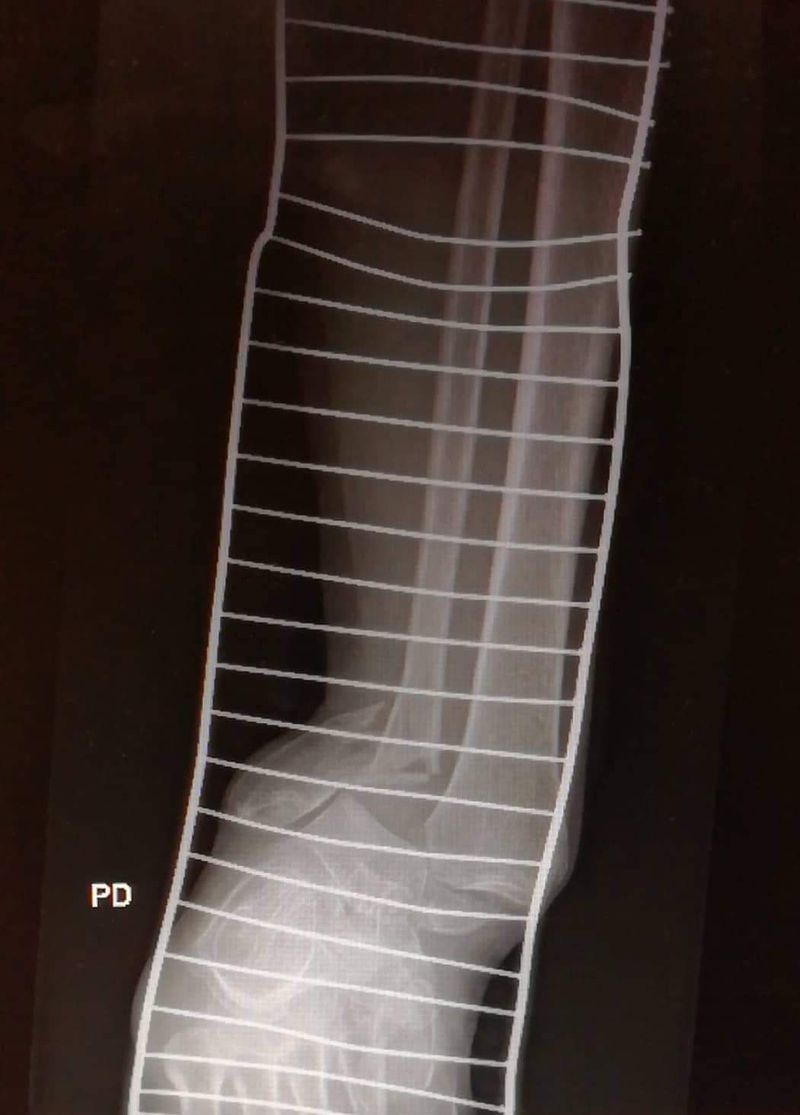

What you see?

What is this supposed to be? Some kind of external fixation of the ankle and lower leg?

No it isn't an external fixation... This splint is used for fixation the fracture, it's just temporary solution in first aid

Comminuted fracture of the tibia

Pilon fracture